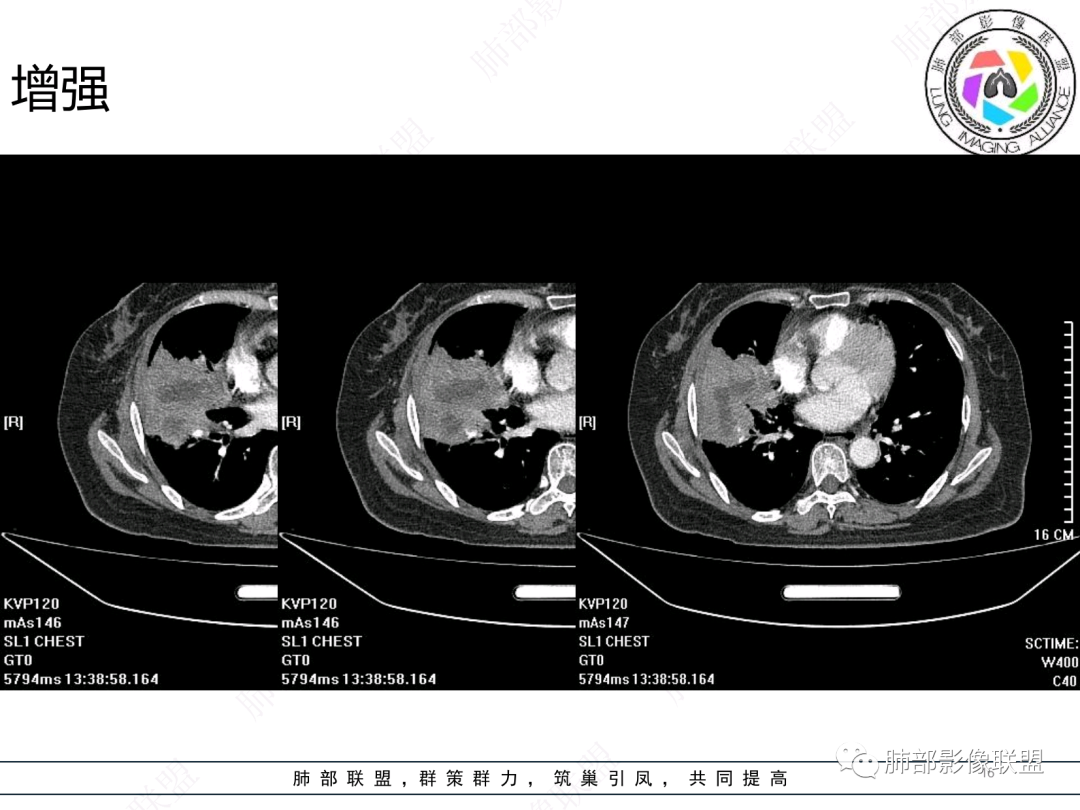

女,74岁,咳嗽咳痰加重一周入院,右肺中叶大片实变影,边界清晰,病灶内密度不均匀,右肺中叶支气管变窄,增强扫描病灶明显强化,考虑恶性病变能,鉴别肺脓肿。

胸部CT:右肺中下叶大片实变影,界清,边缘膨隆为主,中叶外侧段支气管截断。增强不均匀强化,边缘可见血管影迂曲模糊,内见条带状低密度影。治疗后病变进展。考虑恶性,鳞Ca?鉴别TB、OP。

南边:跨叶、楔形/边缘平直、支气管壁无破坏/连续/局部无膨大、实变区肺动脉走形自然、实性部分均匀、延迟强化、坏死腔内壁光滑/内壁强化环/近端与支气管相通,这些点均支持炎性。所以综合分析:符合炎性。